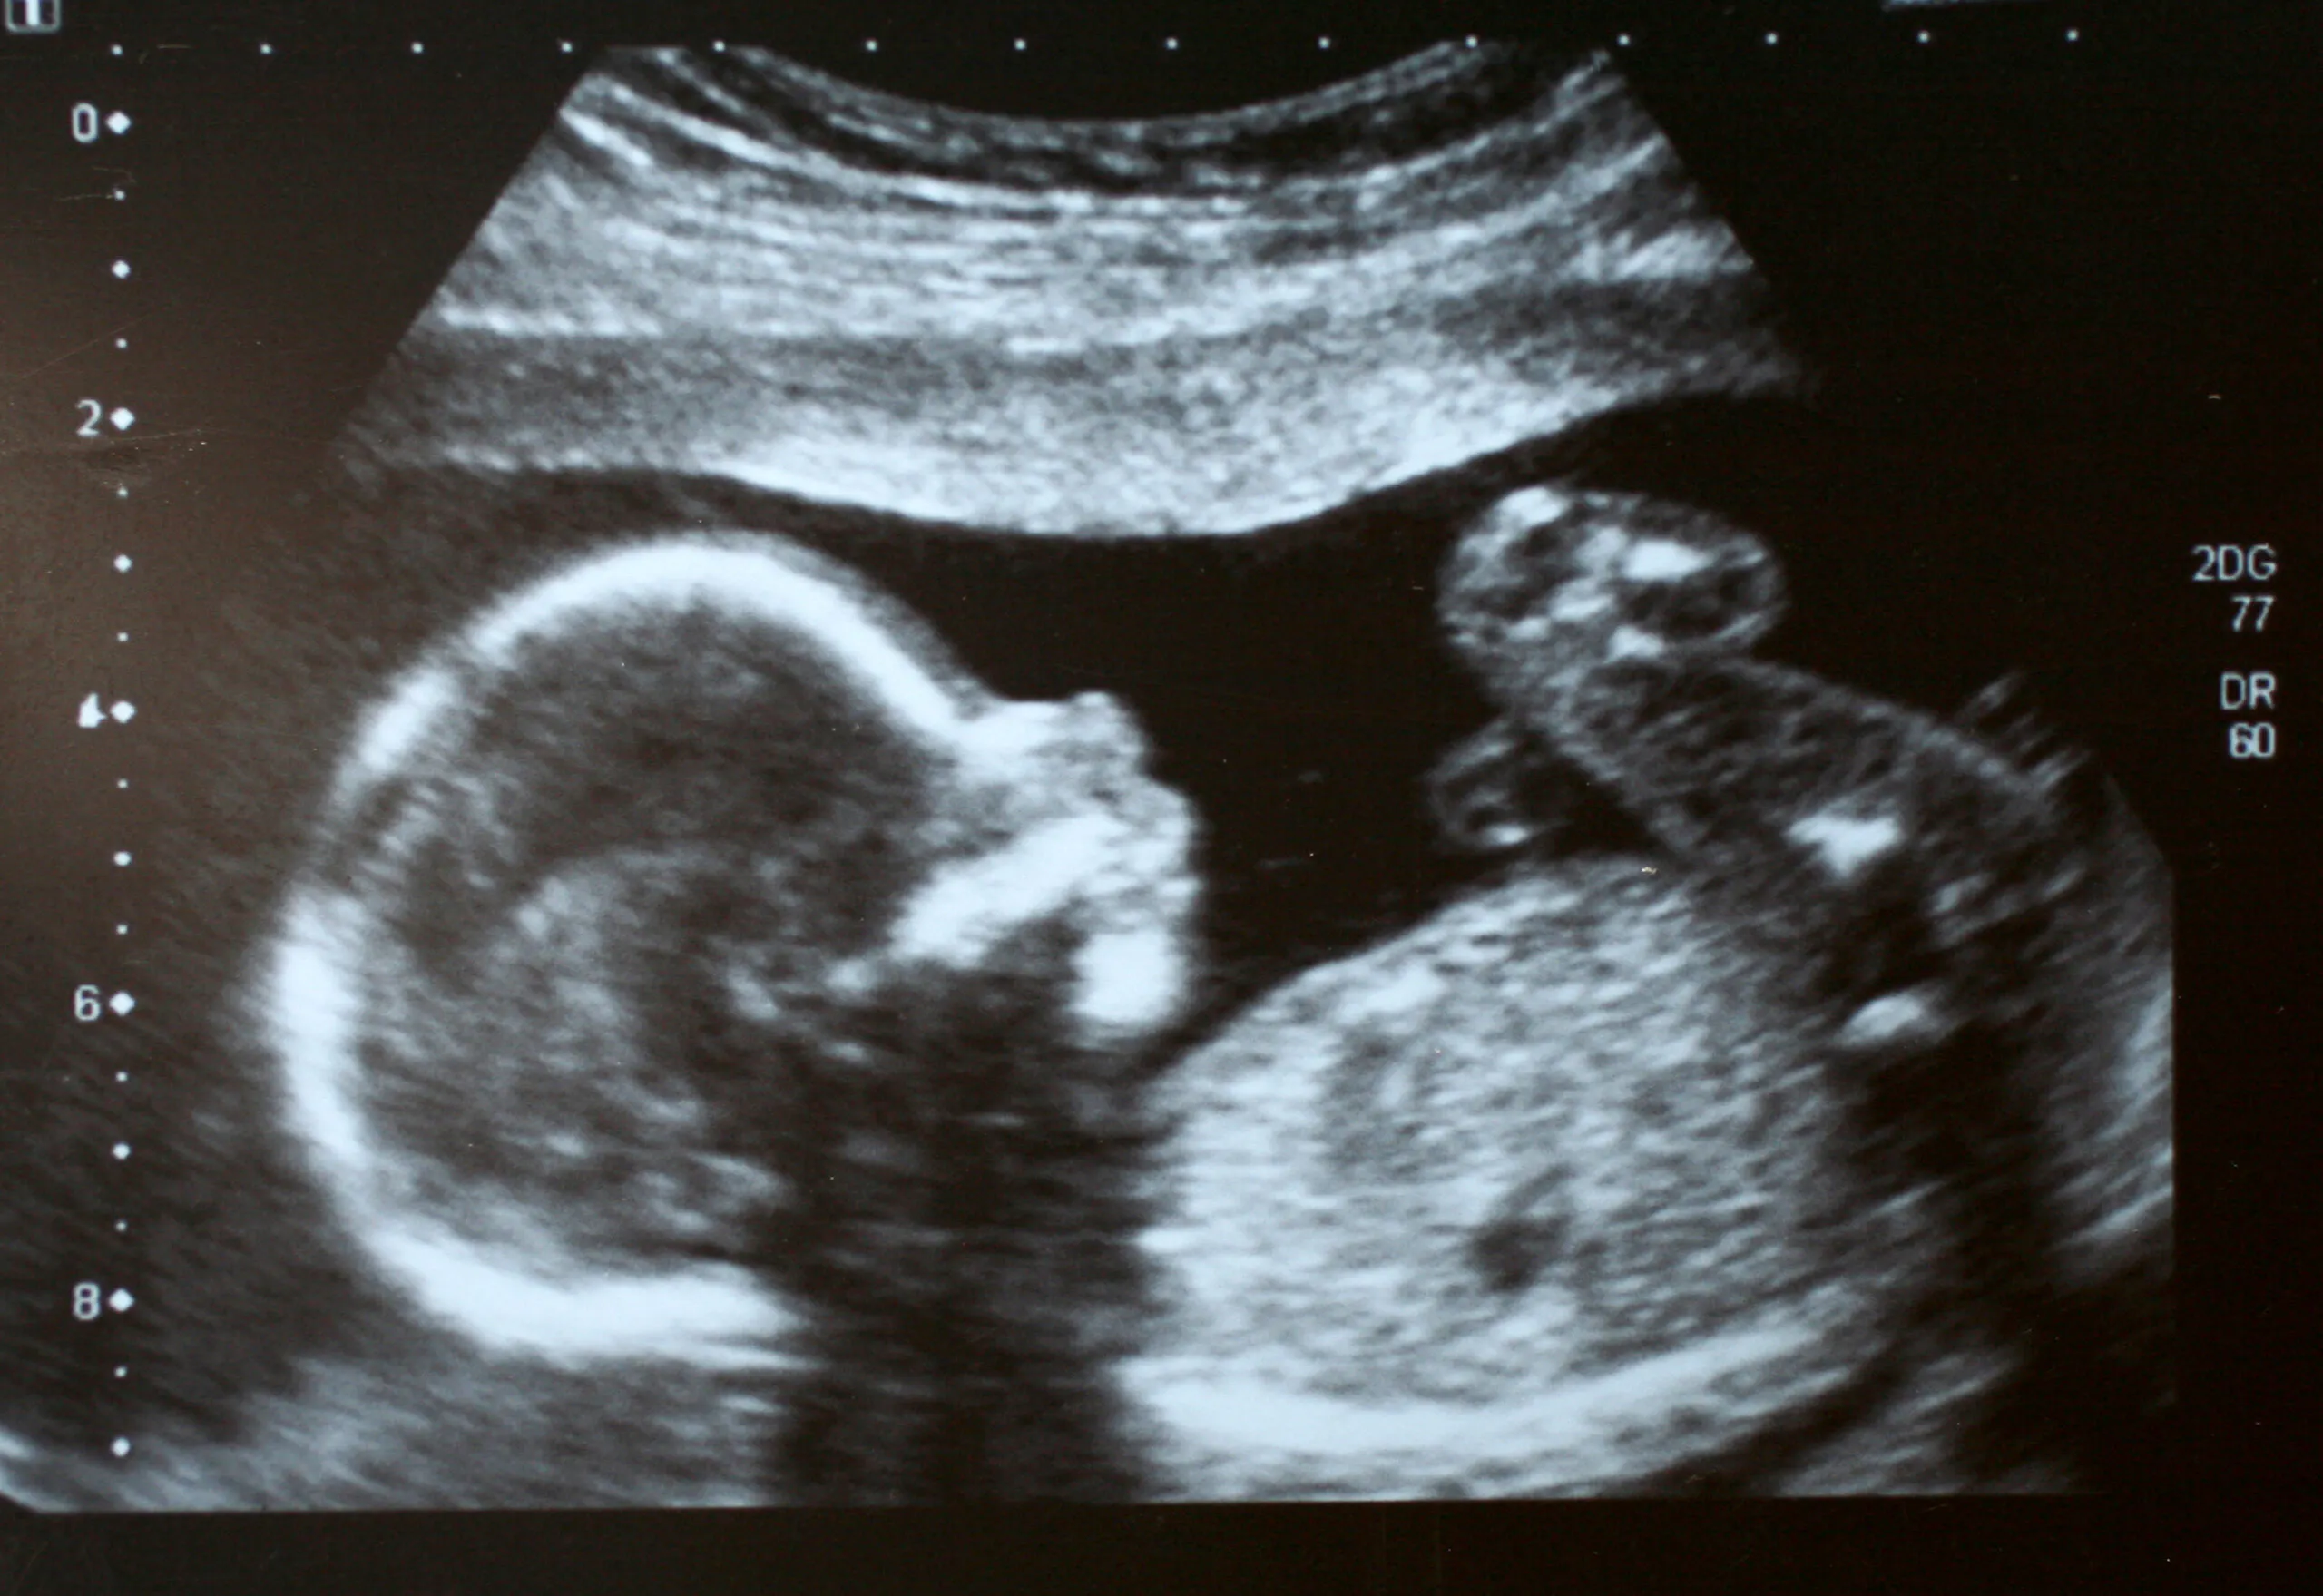

Prenatal life, or fetal personhood, has sparked heavy debate recently between pro-abortion advocates and those protecting the sanctity of life. While abortion rights supporters claim personhood laws could impact in vitro fertilization or subject women to murder charges, pro-life advocates argue that fertilized eggs, embryos, and fetuses should have the same rights as newborns.